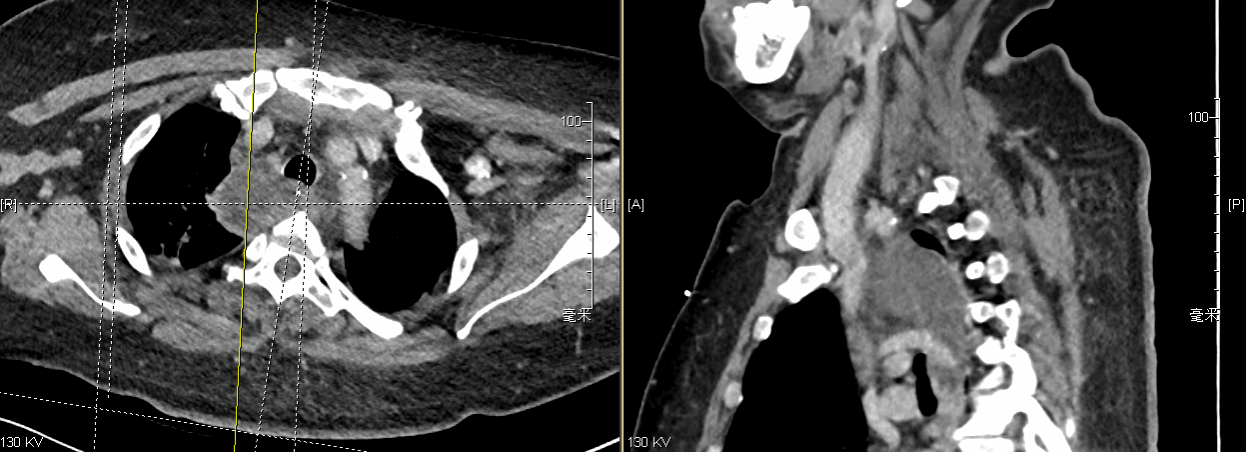

纵隔感染患者胸腔内常存在胸腔感染、脓胸、术中粘连,手术难度大,易导致术中损伤。胸外科常务副主任强光亮主任凭借多年的临床经验,和娴熟、细腻的手术操作技巧,巧妙地利用单操作孔胸腔镜微创手术技术,松解术中粘连,在保护重要脏器、血管的前提下,精准暴露了纵隔区域,将纵隔脓肿彻底切开,通畅引流,并另制作合理切口放置胸腔引流管,完成了北医三院首例纵隔脓肿切开引流术,为患者纵隔感染的消退创造了机会。

图为强光亮团队进行微创手术